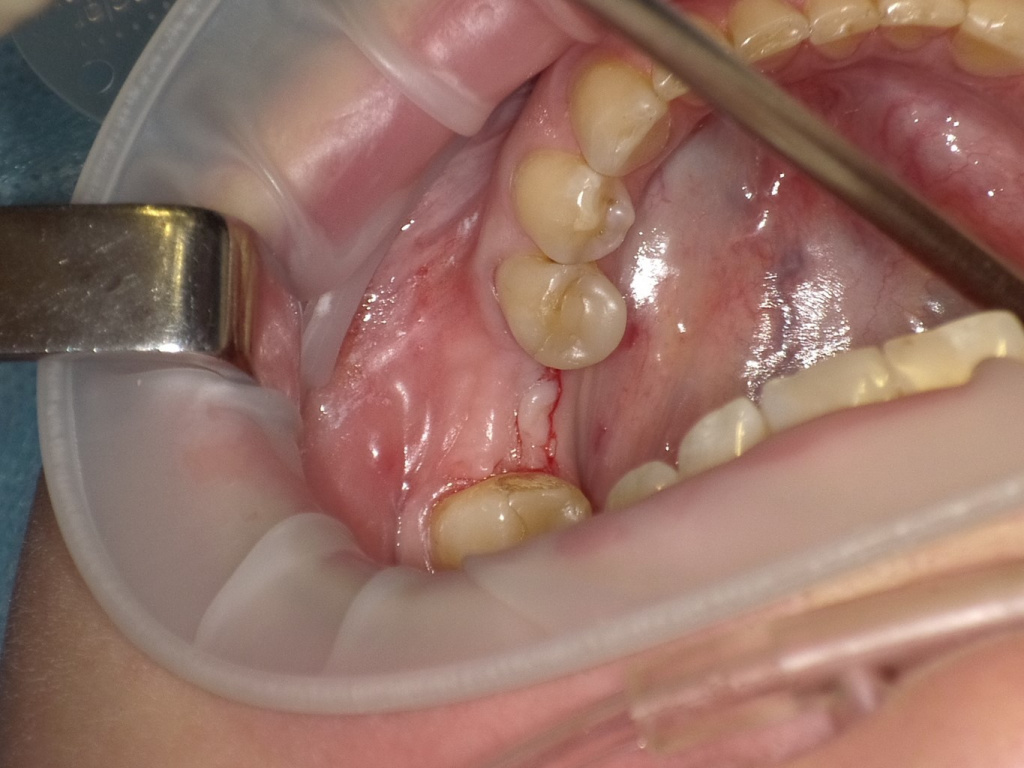

Постановка имплантата после презервации